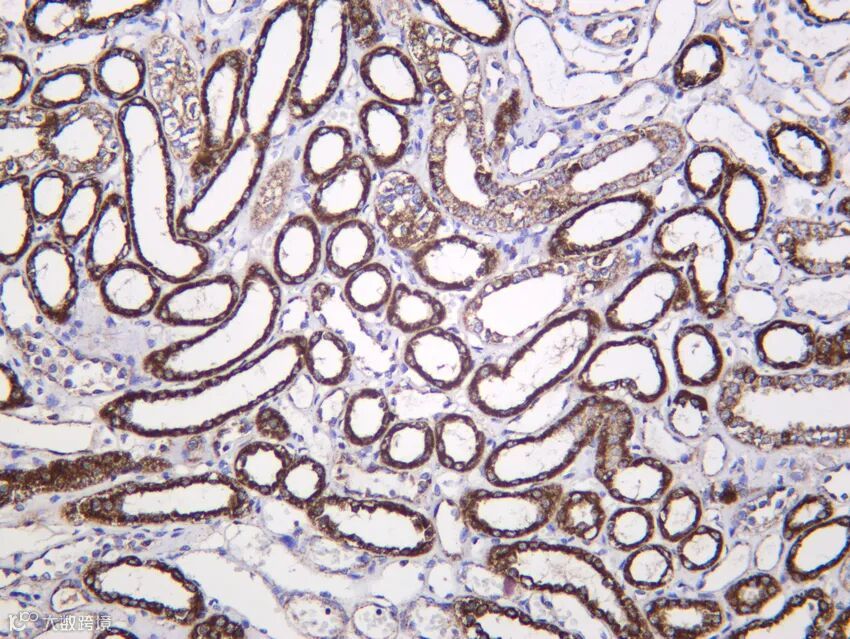

Rab10 (PT1212R) PT™ Rabbit mAb

Reactivity:Human, Mouse, Rat

Applications:WB, IF, IP, ELISA

关键词:小GTP酶、囊泡 trafficking、GLUT4转位

Rab10 是 Rab GTP 酶家族成员,在胰岛素刺激下被激活,调控 GLUT4 储存囊泡向质膜的转运,促进葡萄糖摄取。此外,Rab10 参与初级纤毛形成、自噬体成熟及上皮极性建立。其功能受 DENND4C GEF 和 TBC1D1 GAP 精确调控。Rab10 异常与 2 型糖尿病、纤毛病相关。本抗体跨物种适用,支持 IP 验证互作,是膜运输与代谢研究的重要工具。